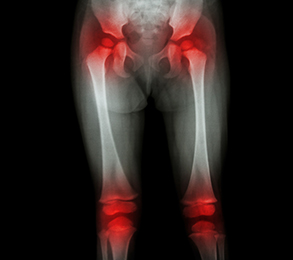

Knees and Hips: A troubleshooting guide to knee and hip pain

Do your knees or hips hurt? Most people will at some point have knee or hip pain because these large joints have a demanding task: they must bear the full weight of your body while at the same time allowing for a wide range of motion. Wear and tear, injury, and simple genetic predisposition can all contribute to knee or hip pain. This Special Health Report Knees and Hips: A troubleshooting guide to knee and hip pain, covers a wide range of knee and hip conditions and describes in detail treatments, preventive strategies, and surgeries.

Your knees and hips are your largest joints. They support your body's weight and must work in close coordination to provide the mobility most people take for granted, until injury, arthritis, or other problems interfere.

Depending on the cause of your pain, the solution might be a set of exercises, pain relief medication, minor surgery, or some combination of these. But for many people, knee and hip problems become so intractable that the best solution is to replace a worn-out knee or hip with a mechanical joint.

If you are reading this report, you probably have knee or hip pain. You’re not alone. According to the CDC, nearly half of all Americans develop knee arthritis by age 85, and a quarter may develop hip arthritis. Injuries to these joints are also common, even at younger ages.

Your knees and hips are your largest joints. While supporting your weight as you stand upright, they must work in close coordination to provide the mobility most of us take for granted. So it’s not surprising, given all that your knees and hips do for you, that they’re prone to injuries and deterioration. As an orthopedic surgeon, I see many patients who have injured a joint because they’ve jumped too quickly into a new sport or workout routine, or have been pushed to exercise too hard. Even if you avoid injuries, you can develop arthritis and other painful conditions from the gradual wear and tear that comes with aging. And increasingly, I see patients whose joints have deteriorated because of the extra weight they carry.